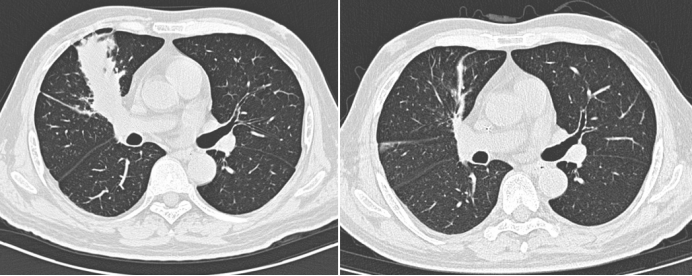

病例2:一例糖尿病酮症酸中毒合并肺毛霉感染患者,病情进展迅猛。此类感染具有显著的特征性表现:与普通细菌感染所致肺炎仅形成肺部阴影不同,毛霉等真菌感染可在肺内或气道中形成侵袭性新生物(图2),这种由大量毛霉菌丝构成的病变组织,相当于在体内生长的"异常生命体"。曾有呼吸科医师曾尝试通过介入技术清除此类病灶,但该操作风险极高。例如本例患者在介入过程中发生大出血,最终死亡。

图片

2  病例2影像学、病理、气管镜下表现